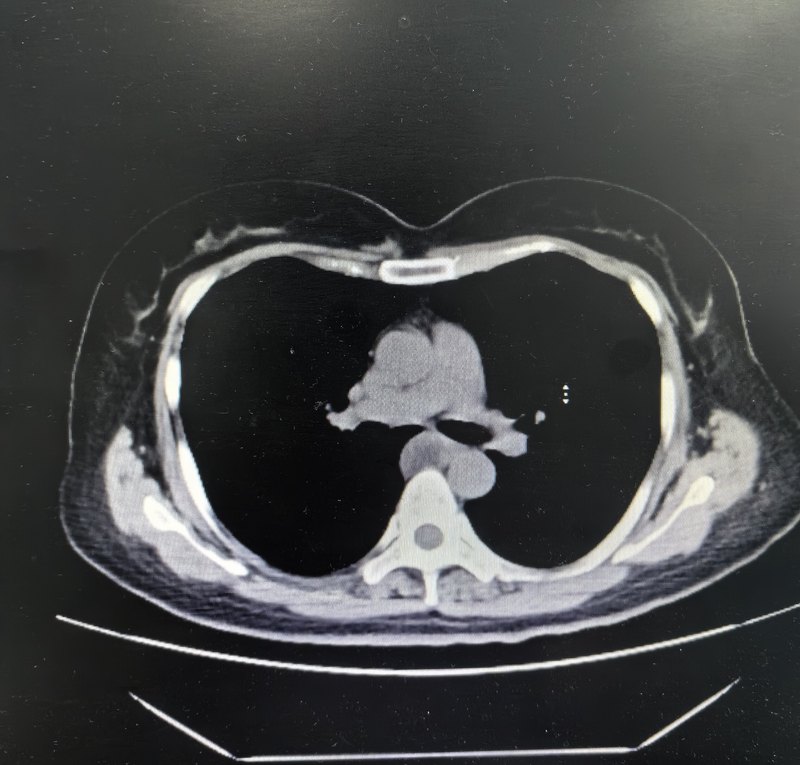

縱隔是一片神秘的地帶,一個(gè)晦澀的概念,就連非胸外科專(zhuān)業(yè)的醫(yī)生也很慢搞的明白,更不用說(shuō)把CT和肉眼所見(jiàn)的景象對(duì)應(yīng)起來(lái)。否則就不會(huì)有這樣一個(gè)差點(diǎn)被化療的胸腺瘤患者了。該患者因?yàn)榭磩e的病恰好需要做胸部CT,發(fā)現(xiàn)前縱隔多發(fā)結(jié)節(jié),說(shuō)是多發(fā),其實(shí)也就三四個(gè),而且緊挨著,其實(shí)是一個(gè)整體有多個(gè)分葉而已。但是有些醫(yī)生就只會(huì)看報(bào)告,不會(huì)分析CT片子,恰好前縱隔可能出現(xiàn)的疾病比較多(比中縱隔、后縱隔多),影像科考慮的復(fù)雜一些,先是建議進(jìn)一步檢查,后來(lái)考慮增大的淋巴結(jié)。于是某內(nèi)科醫(yī)生就診斷淋巴瘤,勸他化療??蛇@位患者正值中年,40多歲,難道就這樣接受癌癥和化療的命運(yùn)嗎?輾轉(zhuǎn)我科,我們一看片子,這不是典型的胸腺區(qū)域嗎?而且沒(méi)有轉(zhuǎn)移,一個(gè)局限的病灶,有可能是侵襲性胸腺瘤,是完全可以手術(shù)切除的??!當(dāng)然腫瘤總體來(lái)說(shuō)也比較大一點(diǎn),和血管有密切牽連(所以說(shuō)考慮侵襲),經(jīng)過(guò)仔細(xì)分離和解剖,所有血管得以妥善處理,腫瘤最終完整切除,而且手術(shù)是單孔胸腔鏡操作,只有一個(gè)3cm的小切口,是胸外科最微創(chuàng)的手術(shù)方式。術(shù)后病理證實(shí),該腫瘤就是胸瘤腫瘤,而且是其中一種特殊類(lèi)型,神經(jīng)內(nèi)分泌腫瘤,該類(lèi)型具有較強(qiáng)的外侵性,且對(duì)放化療不敏感,需要盡早手術(shù)切除??梢韵胍?jiàn),倘若這個(gè)患者年齡再大一些,或者其他原因不找我們胸外科,而是接受化療,最終一定會(huì)耽誤病情,失去手術(shù)機(jī)會(huì)??v隔腫瘤有很多種,但常見(jiàn)的后縱隔腫瘤多數(shù)是神經(jīng)、食管來(lái)源,中縱隔則多數(shù)是支氣管、心包來(lái)源,99.9%是良性,而前縱隔就不一樣了,雖說(shuō)胸腺瘤居多,但是胸腺瘤也已被定性為低度惡性腫瘤,更何況還有胸腺癌、惡性畸胎瘤、精原細(xì)胞瘤等其他惡性可能。當(dāng)然也有可能是這個(gè)CT報(bào)告的淋巴結(jié)增大、淋巴瘤之類(lèi)的。有的CT報(bào)告字眼比較模糊,不寫(xiě)腫瘤,寫(xiě)個(gè)結(jié)節(jié)或者病變之類(lèi)的,那如果只會(huì)看報(bào)告,就耽誤了。所以如果見(jiàn)到“前縱隔“三個(gè)字要注意了,一定要找會(huì)分析CT片子的醫(yī)生,而且多找?guī)讉€(gè)看。